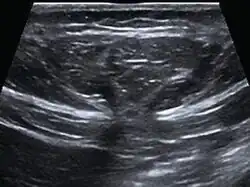

Abdominal ultrasound of a midline epigastric hernia.

Ultrasonography is also used for diagnostic purposes.